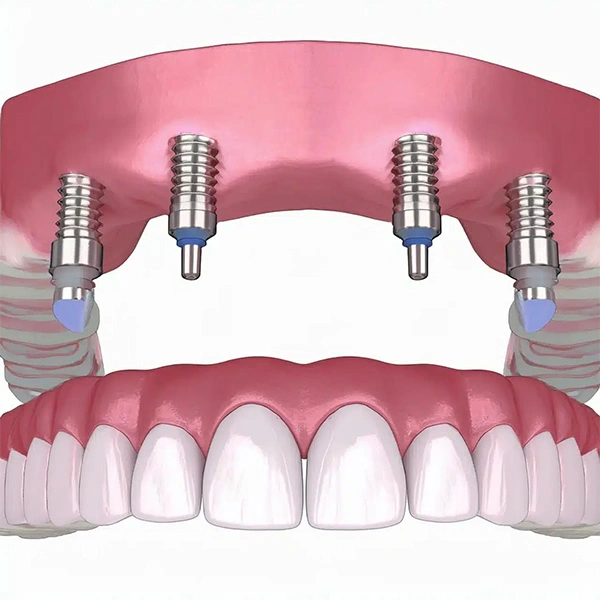

- Impianti Dentali: Soluzione definitiva per sostituire uno o più denti mancanti, ripristinando la funzionalità masticatoria e l’estetica del sorriso.